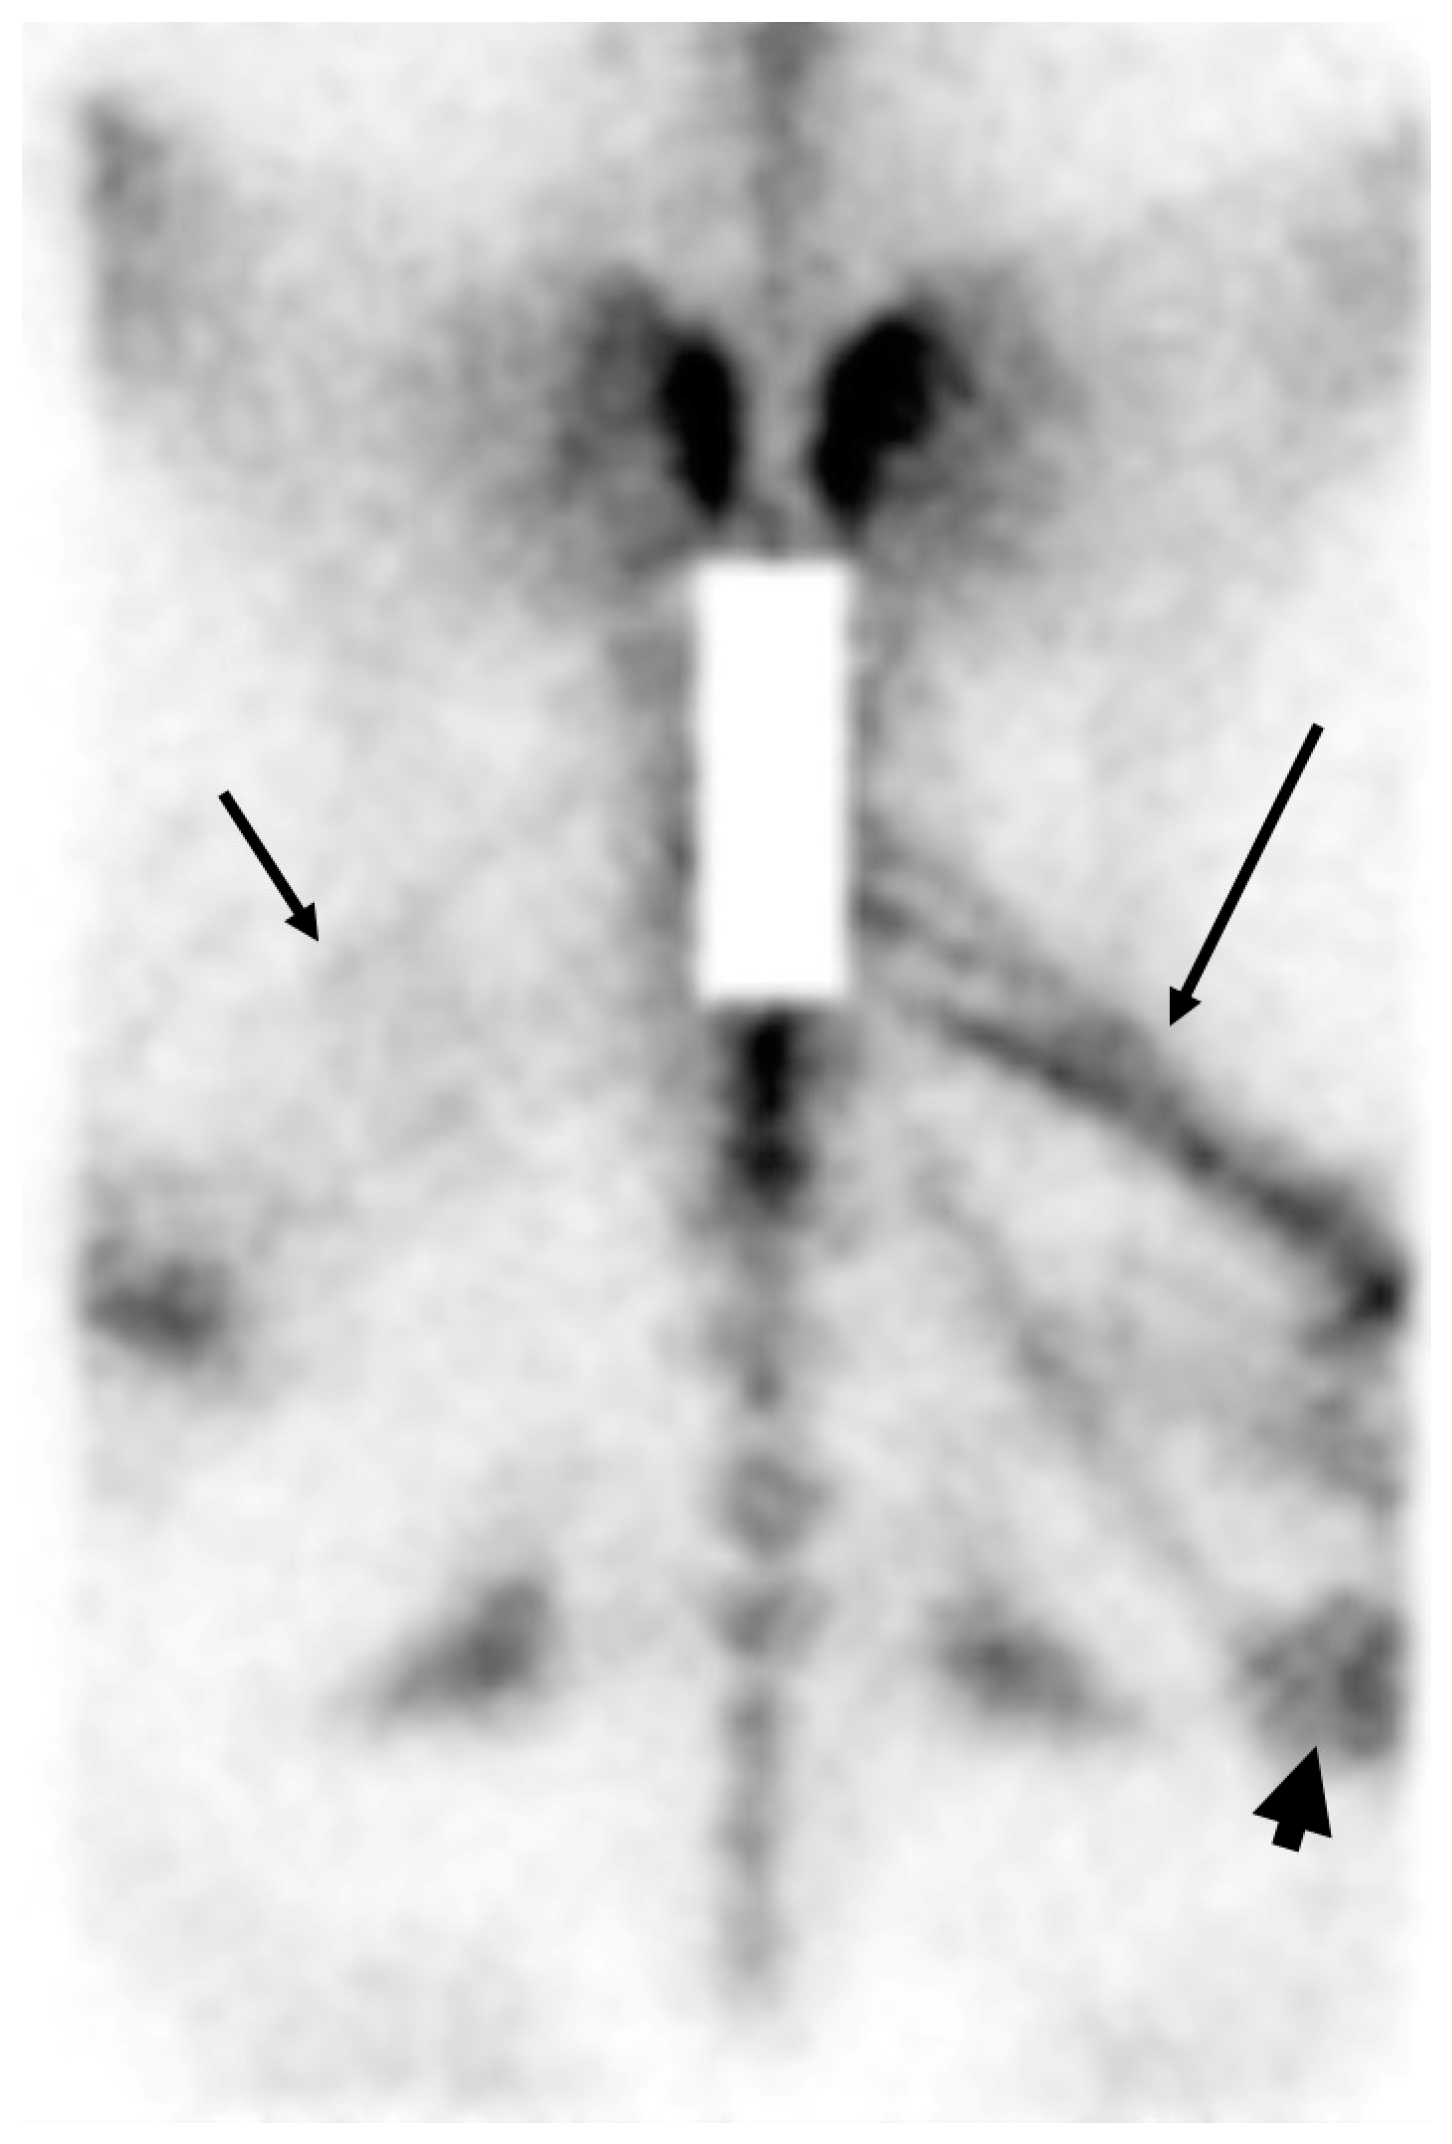

3.1. Imaging of Vertebral Column, Ribs and Proximal Limbs

3.2. Scintigraphy Combined with CT and MRI